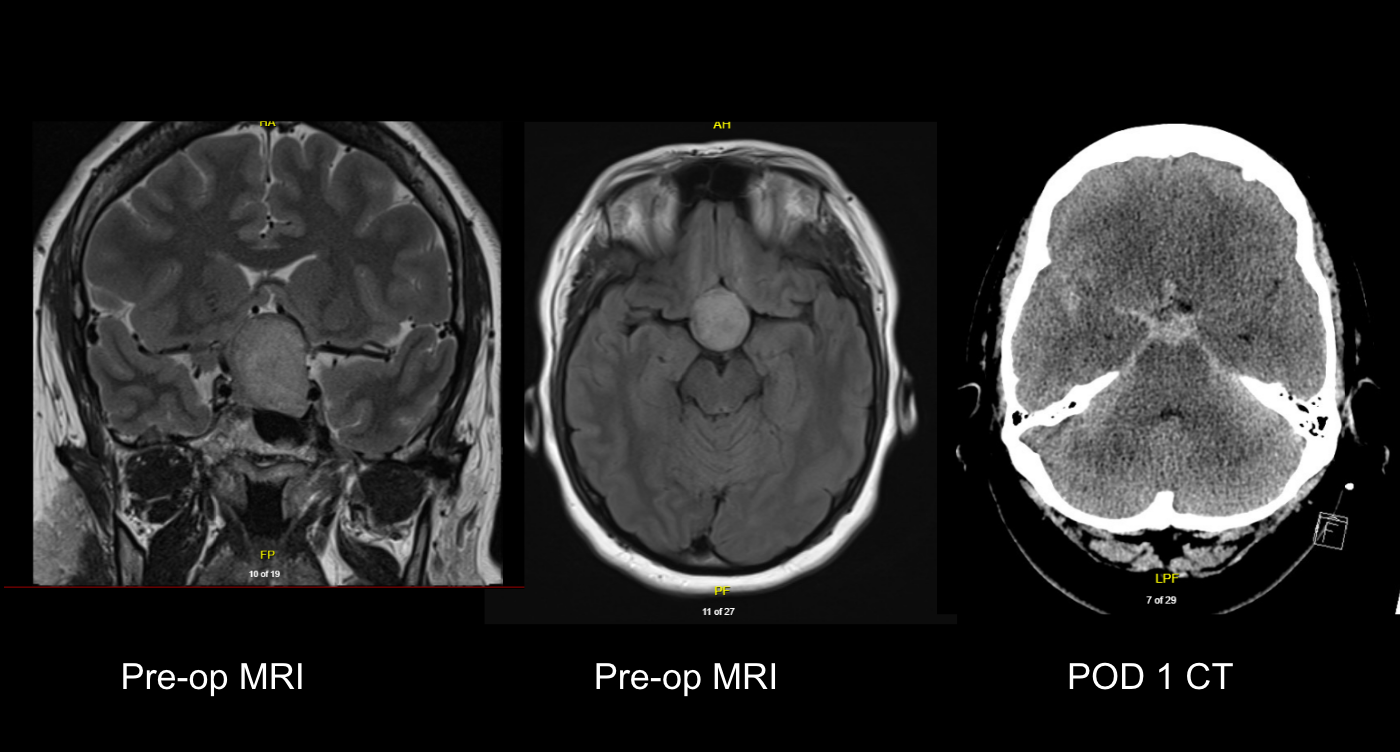

Model Structure: A Markov model with a one-month cycle length and lifetime horizon (30 years) was developed and used to capture the costs and outcomes associated with lecanemab + SoC and SoC alone when treating early AD (Figure 1). The model included four distinct health states based on disease severity according to Clinical Dementia Rating – Sum of Boxes (CDR-SB) (replicated in the community and institutional care settings) and death (ie., nine health states in total).

Figure 1. Model structure

Model structure

Dashed and solid lines are both used to denote possible transitions.

Click here to view additional details on the model structure, mortality inputs, and institutionalization inputs

AD Progression: Transition probabilities for the MCI due to AD and mild AD health states for the first 18 months are based on the CDR-SB baseline and 18-month distributions from Clarity AD. Beyond 18 months, an estimate of treatment effect for lecanemab vs. SoC from Clarity AD (hazard ratios based on time to worsening of CDR-SB: 0.729 (95% CI: 0.604 - 0.881; p=0.00105) was applied to the MCI and mild AD transition probabilities informed through published natural history data (Potashman et al).18 Transition probabilities for the moderate AD and severe AD health states were informed through natural history data for the full time horizon of the analysis, due to lack of sufficient data on these health states from Clarity AD.

Click here to view monthly transition probabilities

Impacts to Patient and Caregiver Quality of Life: The societal perspective included both patient and caregiver utilities. Patient and caregiver health state utilities were sourced from Landeiro et al. (2020)22 and Lopez-Bastida et al. (2006)23, respectively. Utility decrements from Farina et al. (2020)24 were applied to both patients and caregivers to capture impact of a patient’s care setting (entering institutional care) on health related quality of life (-0.16 and -0.09 for patients and caregivers, respectively). Utility decrements for patients incurring AEs (infusion-related reactions, ARIA-E, and ARIA-H events) were also included.

Click here to view patient and caregiver health state utilities

Costs: Costs included for the societal perspective included those for caregiver direct medical and non-medical care, caregiver productivity loss, drug acquisition and administration, disease management, diagnostic, adverse events, and patient direct medical and non-medical care.

Click here to view additional descriptions of each cost category

RESULTS

• In the base case, lecanemab + SoC was more costly ($77,812) and more effective (1.19 gain in quality adjusted life years [QALYs]) than SoC alone, resulting in an incremental cost utility ratio (ICUR) of $65,424 per QALY (Table 1)

• The probability that lecanemab was cost-effective at a threshold of CAD100,000 was an estimated 95.1% (Slideshow 1)

• Model results were generally stable across a variety of scenario analyses, including those in which key clinical inputs were varied

Table 1. Summary of Base Case Probabilistic Results

Lecanemab + SoC

SoC

Incremental

Total life years (LYs)

8.14

7.48

0.66

Total QALYs

10.59

9.41

1.19

Incremental Costs

$146,219

$68,407

$77,812

ICER (Cost/LY)

$118,356

ICUR (Cost/QALY)

$65,424

CONCLUSIONS

• Lecanemab represents a cost-effective option for the treatment for early AD from the Canadian societal perspective

• Compared with SoC alone, lecanemab + SoC was more costly (CAD 77,812) and more effective (1.19 QALYs) over a lifetime, with an ICUR of CAD $65,424 per QALY gained

• The cost-utility analysis will be further informed by new long-term data as it becomes available (ie., Clarity AD OLE)

Given the considerable body of evidence to support the impact of AD on a patient extending to caregivers, it is important to consider the societal perspective, which can provide added context for decisions regarding reimbursement of lecanemab